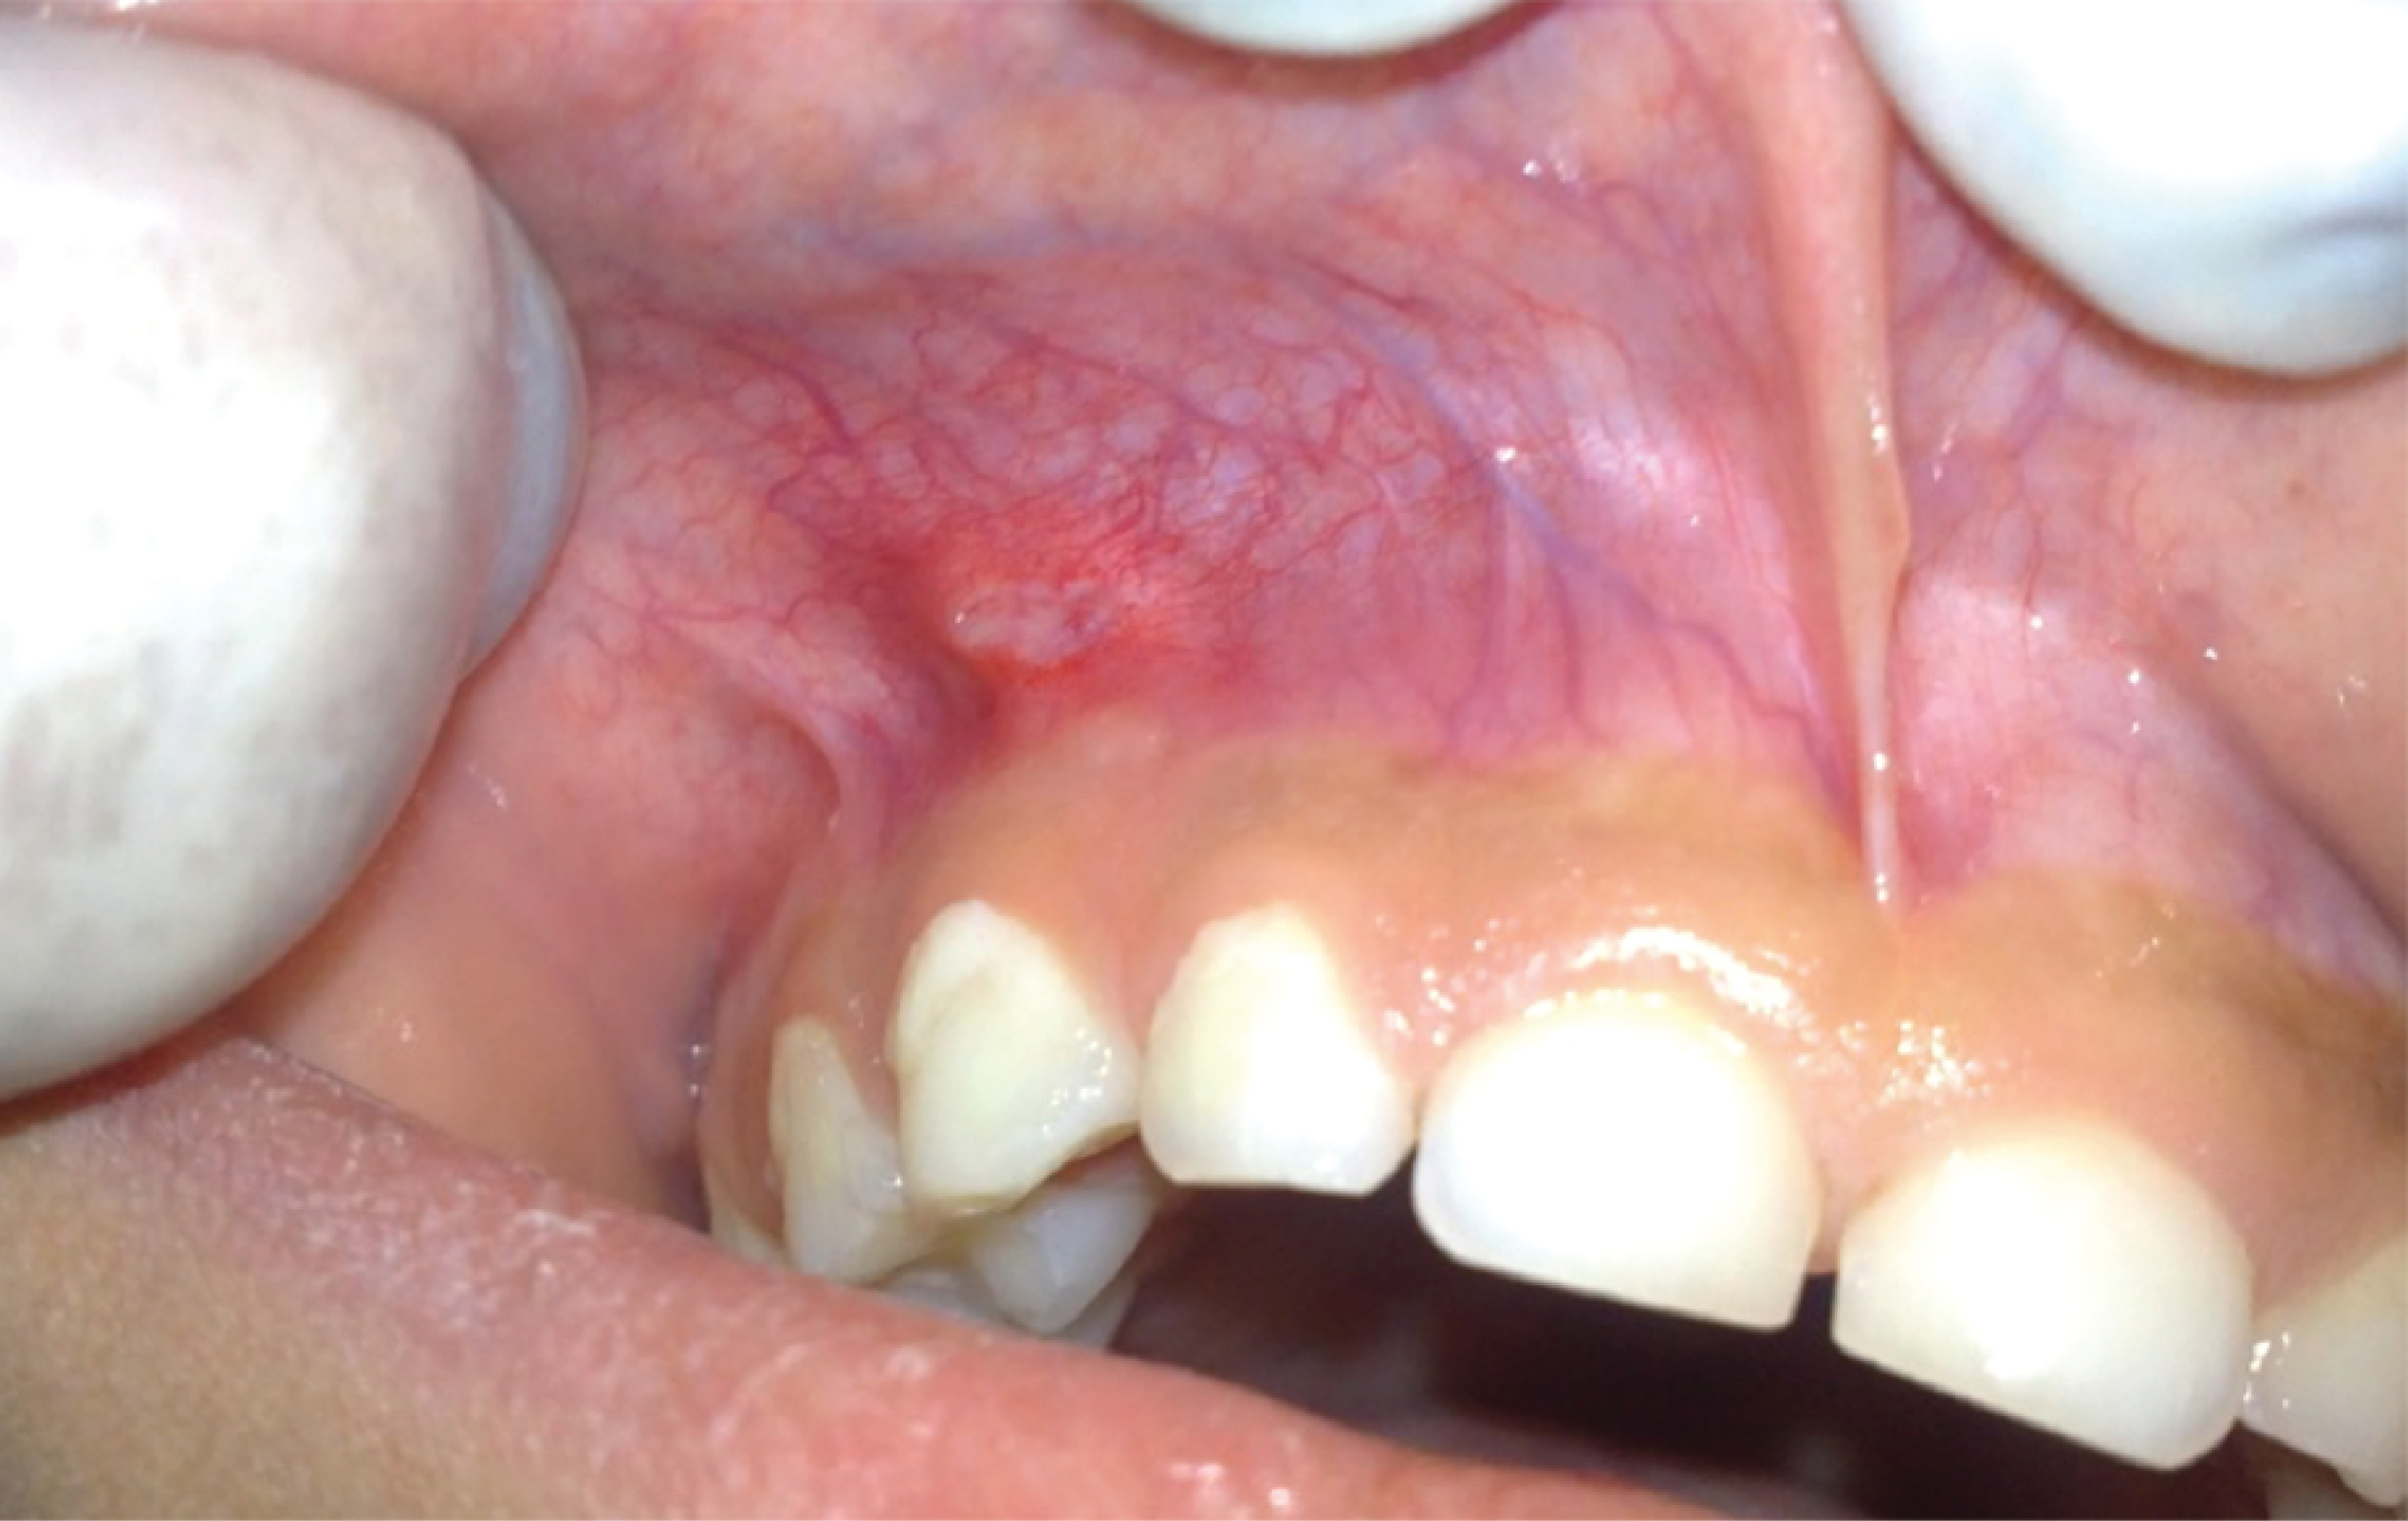

Figure 2